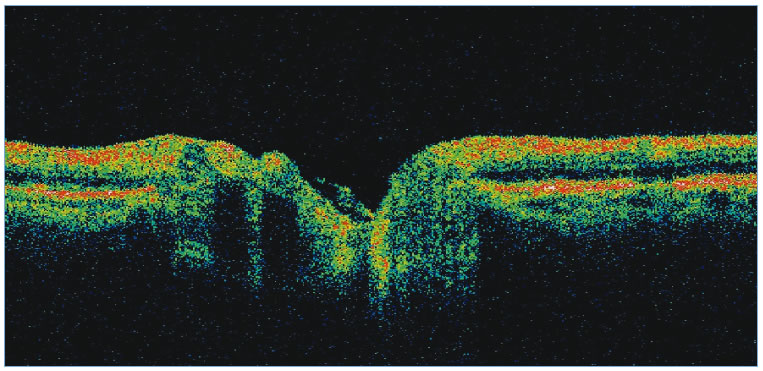

To evaluate the topographic information a contour line defining the disc margin is drawn by the examiner around the inner margin of the peripapillary scleral ring. The HRT software then establishes a reference plane 50 μm posterior to the retinal surface at the papillomacular bundle. The reference plane is established at this location because the fibers in the papillomacular bundle are thought to be least affected as glaucoma progresses, thereby providing a stable reference plane. As displayed in Figure 3, all structures below the reference plane are considered to belong to the optic cup (red) and all structures above the reference plane and within the contour line are considered to belong to neural rim (blue).

Stereometric parameters of optic nerve head topography are generated relative to the reference plane and include rim area, rim volume, cup area, cup volume, cup-to-disc ratio, mean RNFL thickness, and RNFL cross-sectional area. Parameters independent of the reference plane include mean and maximum cup depth, height variation contour, and cup shape measure (the statistical third moment of the distribution of all cup depth measurements). A characteristic sign in normal discs is the configuration of the contour line height display that demonstrates a double hump pattern corresponding to the thicker distribution of nerve fibers along the superior and inferior poles of the ONH (Fig. 4). Glaucomatous structural damage is characterized by a reduction of parameters that describe rim structures (area, volume) and indicate tissue loss (cup shape measure, cup volume, cup-to-disc ratio, cup steepness). As shown in Figure 5, glaucomatous alterations are typically associated with an asymmetrical or diffuse flattening of the contour line, or localized depressions corresponding to disc notches.